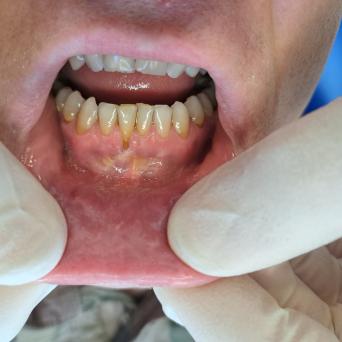

Les personnes souffrant de TCA – anorexie, boulimie, hyperphagie boulimique – ont un risque accru de mortalité par suicide ou par troubles métaboliques par rapport à la population générale. Plus le repérage est précoce, meilleur est le pronostic. Quels sont les facteurs de risque et les changements de comportement évocateurs ? Quel bilan initial ? Quelle prise en charge ?